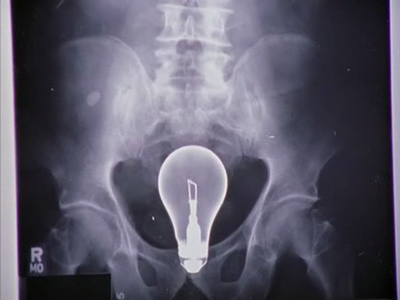

Всратый челендж, или игры с 200- ваттной лампочкой

Главное, чтобы не так

Иллюстрация к комментарию

"-Либо у этого парня лампочка в заднице. Либо в его толстой кишке возникла гениальная идея."